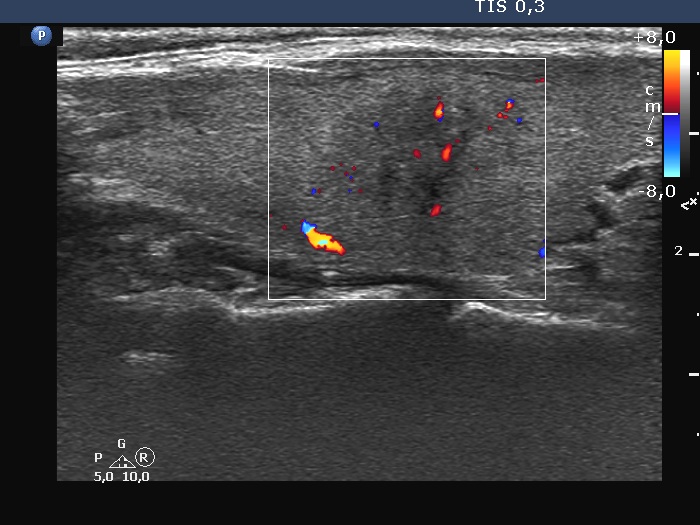

Ultrasonography. The thyroid was echonormal. There were three discrete lesions in the right lobe while several others in the left lobe. There was only one remarkable among them. This was in the ventral part of the right lobe. It was minimally hypoechoic, presented with partly irregular, partly blurred borders. Intranodular vascularity was detected.